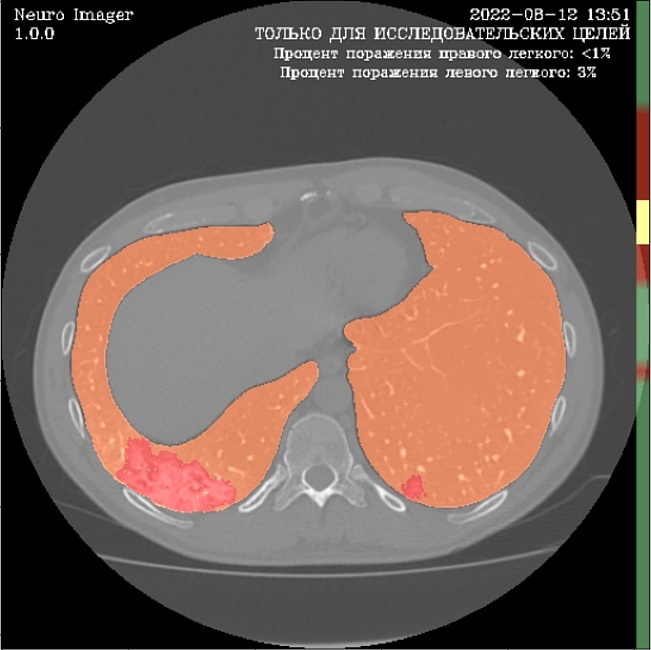

Ниже снимок КТ органов грудной клетки, обработанный модулем для диагностики COVID-19 системы iPavlov CDSS Neuro-Imager: